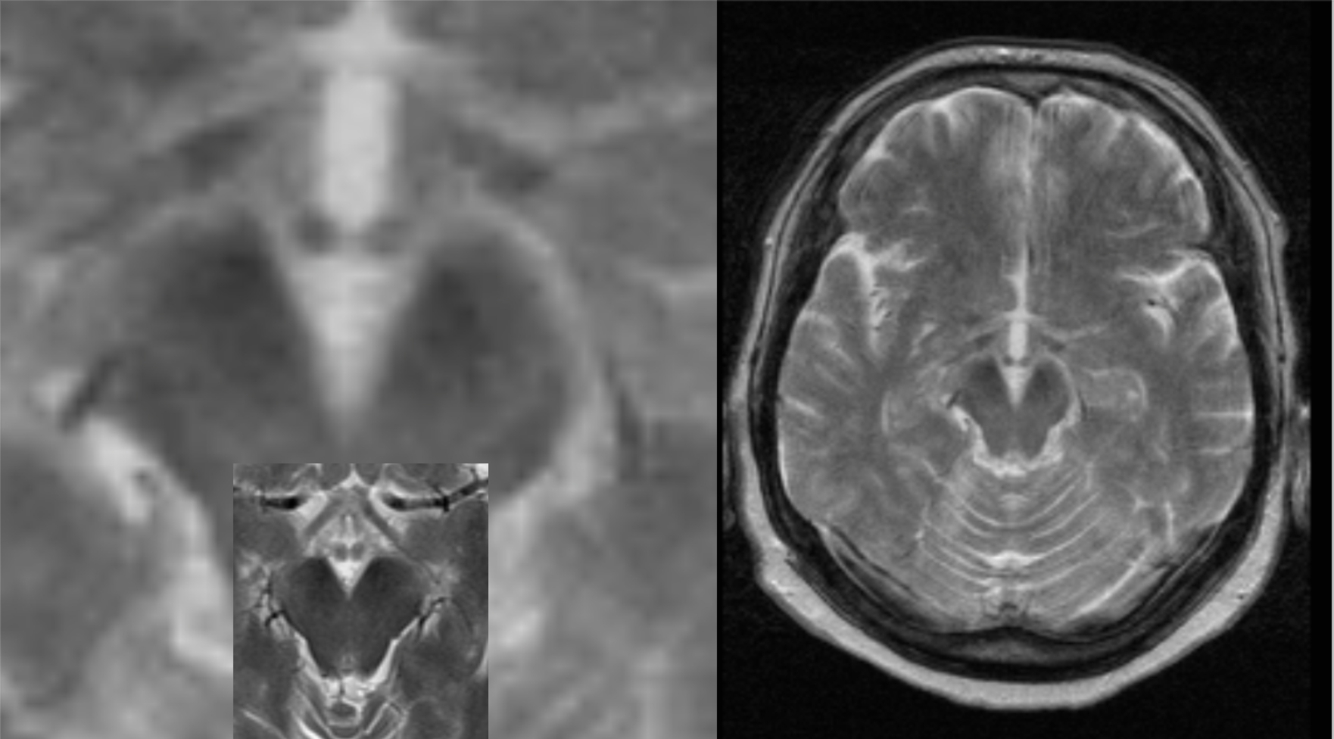

65 y/o alcoholic with confusion. The smaller, inset image is a normal MRI for comparison.

Wernicke’s encephalopathy